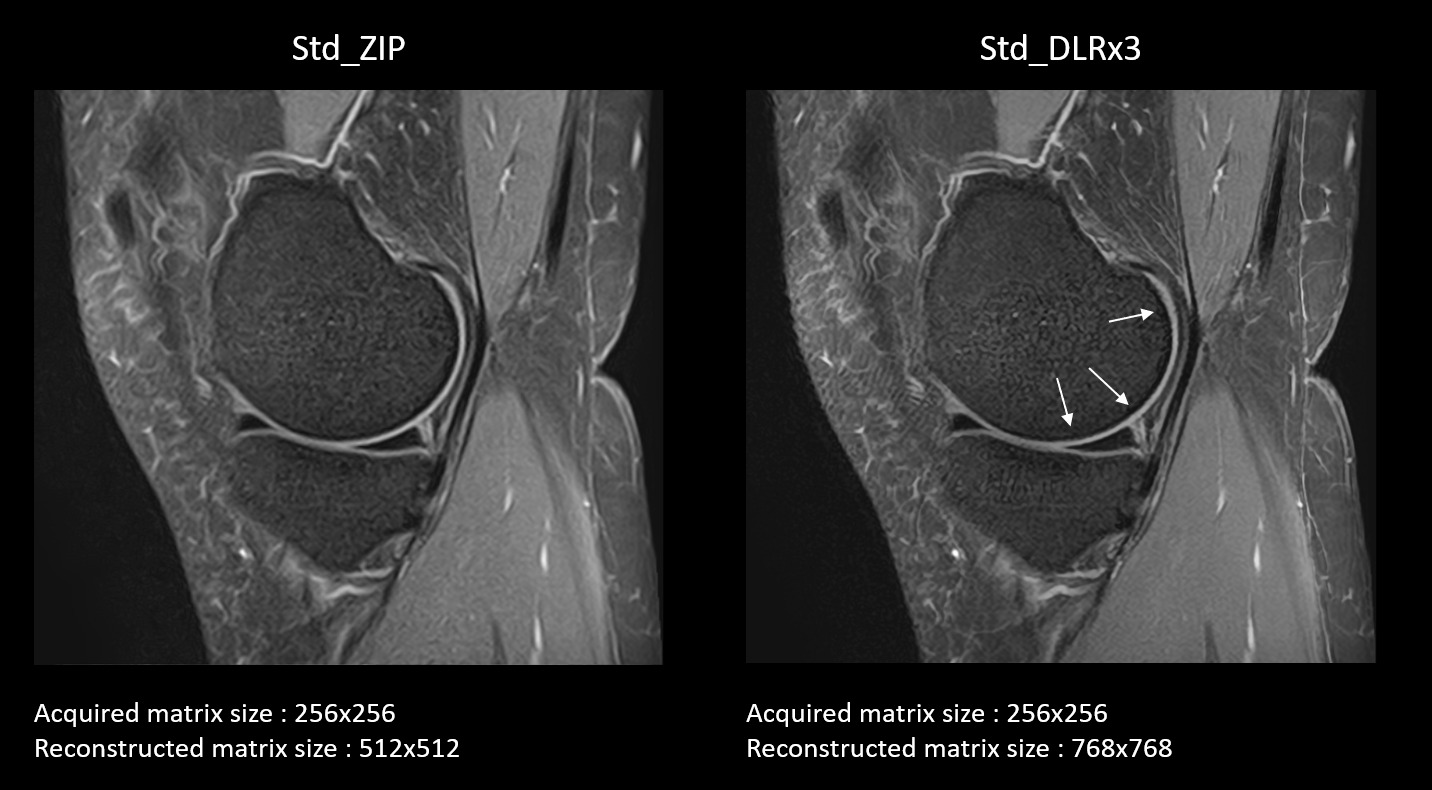

Typical images for the third pairing at 1.5T are shown in figure 2. Pooled scores and Wilcoxon analysis for 1.5T and 3T were plotted in figures 3 and 4, respectively. All images were ranked over score 3, meaning all were considered acceptable for clinical use. When comparing reconstructions for similar scans, performed with low (1st pairing: Low_DLRx2 vs Low_ZIP) or standard (3rd pairing: Std_DLRx3 vs Std_ZIP) acquisition matrix size, image sharpness and forced-ranking were significantly better for the DLR pipeline compared to the ZIP reconstruction, for both magnetic fields. For low matrix size acquisitions, more significant differences were found at 3T while for standard matrix size acquisitions, most scores were significantly different for both magnetic fields, highlighting the superiority of the DLR pipeline compare to the ZIP reconstruction. The second pairing (Low_DLRx3 vs Std_ZIP) was selected to evaluate if faster scans combined with the DLR pipeline could reach the same level of quality as ZIP. For this comparison, not many significant differences were found while forced-ranking was higher for DLR images. These results mean that fast scans with low acquisition matrix size and reconstructed with the DLR pipeline can reach the quality of standard scans and be preferred by radiologists. Finally, no difference in image ringing scores were identified in any of the 3 comparisons and for any fields. For this criterion, all images were scored between 4 and 5, meaning that very few Gibbs ringing artifacts were evident in the evaluated images. Additional study including ZIP reconstructions with upscaling factor of 3 would be needed to better evaluate the putative DLR pipeline superiority to reduce these artifacts further.

Figure 2 : Typical sagittal PD FS images performed with a conventional protocol (Std) at 1.5T. The same scan has been reconstructed with ZIP method (left) and with the DLR pipeline (right). The latter seems to lead to sharpness gain in most structures, especially visible around the cartilage (white arrows).